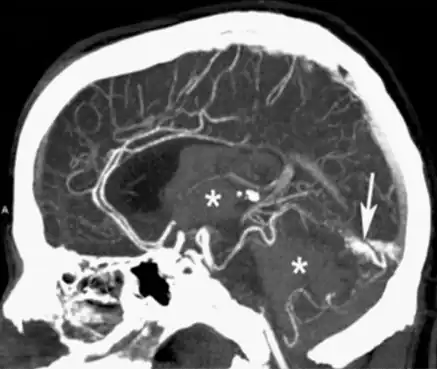

Brain and neck vessels

CTA can be used assess acute stroke patients by identifying clots in the arteries of the brain.[2] It can also be used to identify small aneurysms or arteriovenous malformation inside the brain that can be life-threatening. While CTA can produce high quality images of the carotid arteries for grading the level of stenosis (narrowing of the vessel), calcium deposits (calcified plaques) in the area where the vessels split can lead to interference with accurate stenosis grading. Because of this, magnetic resonance angiography is used more often for this purpose.[3] Other applications of CTA are identifying moyamoya disease, dissections of intracranial arteries, detection of carotid-cavernous fistula, planning for intracranial-extracranial bypass surgery, and involvement of brain tumours such as meningioma with surrounding intracranial vessels.[7]